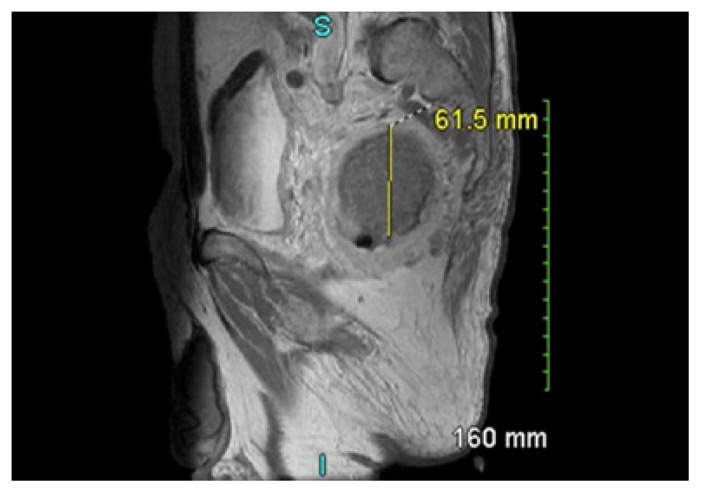

An Alteration to Standardized Treatments: Defunctioning Colostomy in Ultra-Low Stage IIIC Rectal Adenocarcinoma.

Abstract Image